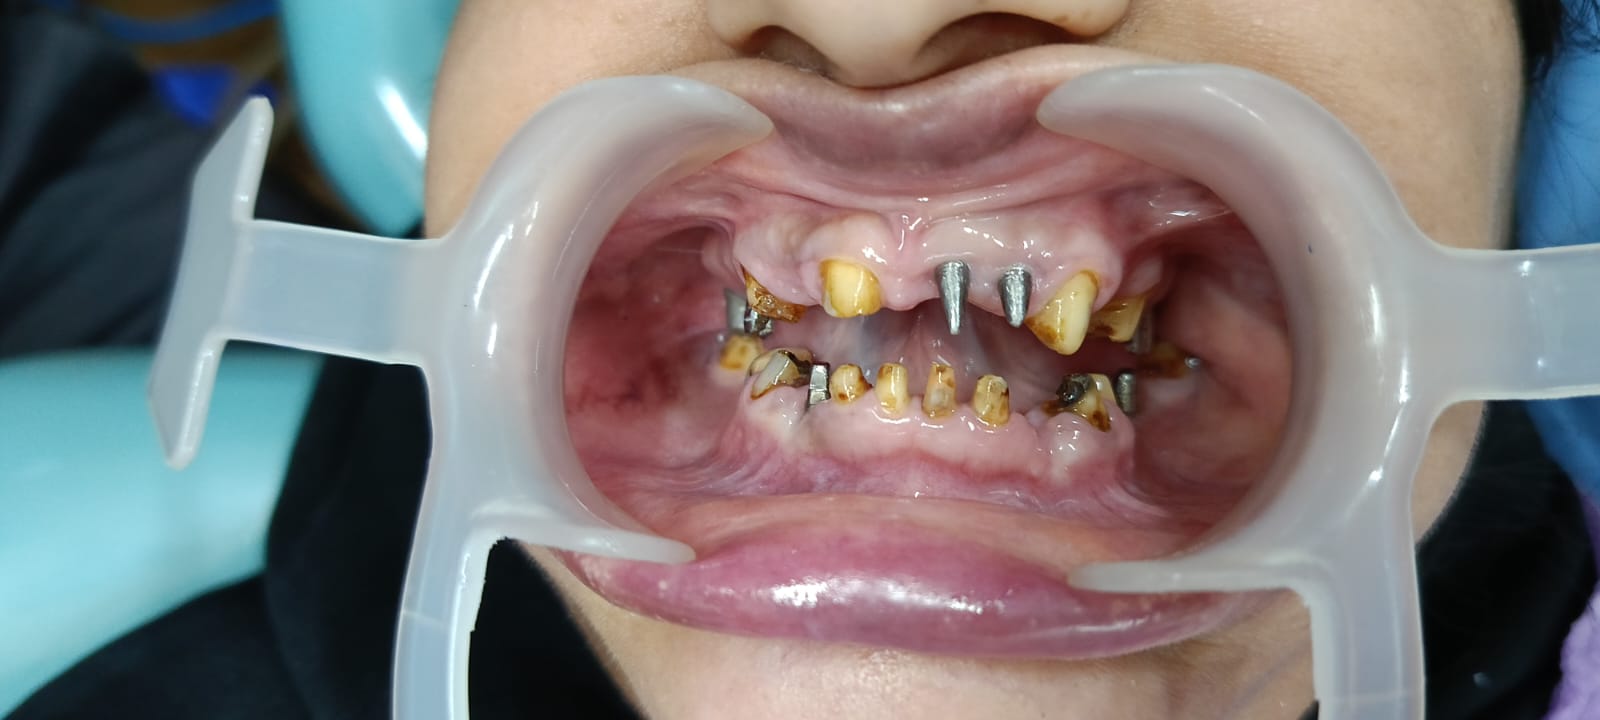

Before